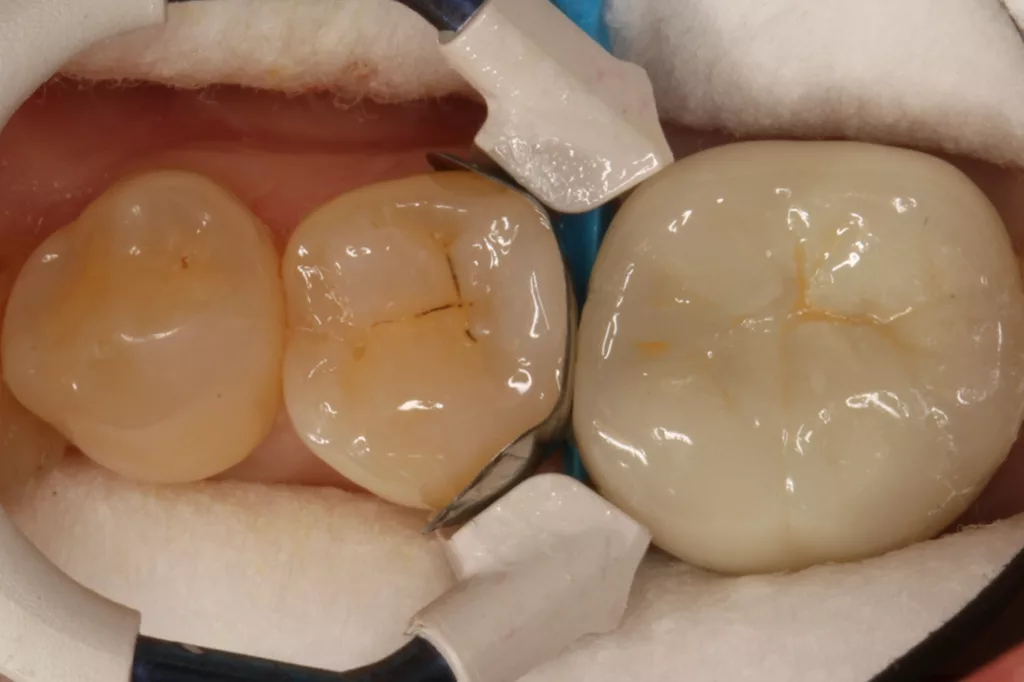

Auch im Molarenbereich können Bulkflow-Materialien effektiv und ökonomisch eingesetzt werden, ohne Abstriche an der Ästhetik machen zu müssen, was der Fall des hier versorgten Zahnes 46 bei einer 22-jährigen Patientin zeigt. Die Abbildung 24 stellt die bereits präparierte und mit einem Einzelzahnkofferdam isolierte Kavität mit der Phosphorsäurekonditionierung der Schmelzränder (Gel Etchant, Kerr) dar. Die Entscheidung zur absoluten Trockenlegung fiel aufgrund der nicht so einfach kontrollierbaren Zunge und der vielen Schluckreflexe, was das Risiko einer ungewollten Speichelkontamination der Klebefläche unverhältnismäßig erhöhte.

Die Verwendung des Kofferdams ist generell eine sehr empfehlenswerte, aber keine zwingende Voraussetzung zur Etablierung einer suffizienten Kontaminationskontrolle [47,96]. Das bisher auch bereits verwendete Zwei-Schritt-Universaladhäsiv G2 Universal wurde hier in der selektiven Schmelzätztechnik angewendet, d.h., das Material arbeitet auf dem Dentin selbstkonditionierend (Abb. 25). Die bislang zu diesem innovativen Mehrflaschen-Universaladhäsiv publizierten Daten zeigen eine beeindruckende Performance, die den Vergleich mit sogenannten Goldstandards [98] wie einem Optibond FL nicht scheuen müssen [13,18,34,58,63,114,119,127,130]. Im nächsten Schritt wurden die einzelnen Höcker mit dem angenehm standfesten Flowable aufgebaut (Abb. 26). Die Abbildung 27 zeigt die komplett versorgte okklusale Kavität, die Abbildung 28 die Situation unmittelbar nach Ausarbeitung und Politur. Erneut beeindruckt die gute Farbadaptation.